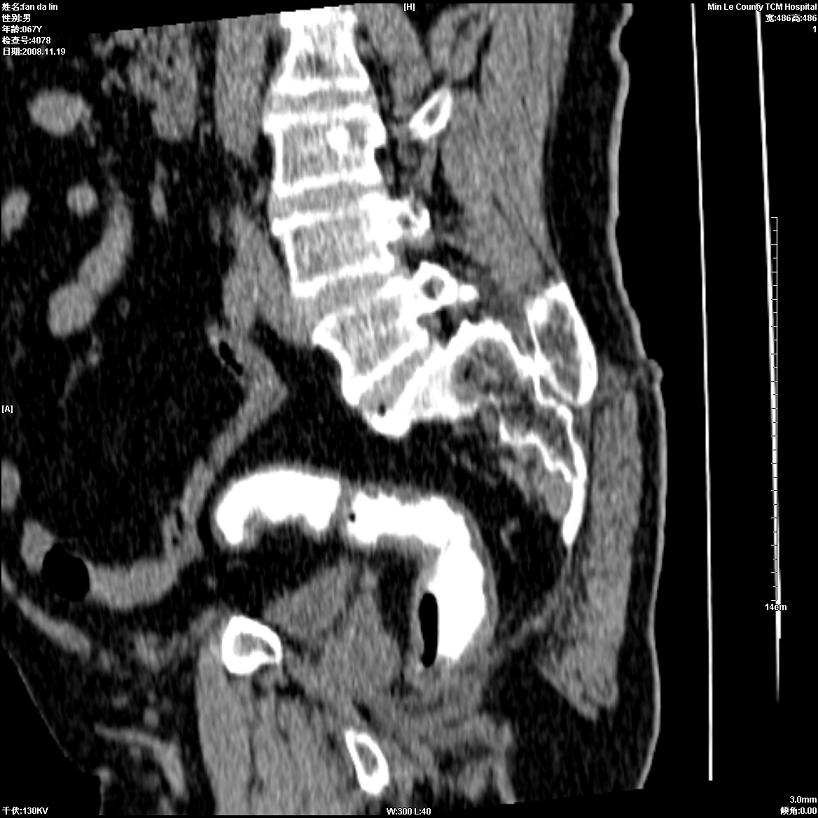

标题: CT16698:M67Y,看看直肠下端是不是病变 [打印本页]

标题: CT16698:M67Y,看看直肠下端是不是病变

粘膜皱壁,不除外内痔

直肠及乙状结肠管壁均增厚,考虑炎症.

直乙交界处肠壁不规则增厚,还是做个肠镜吧

只是肠壁局限性增厚,但难说明问题。